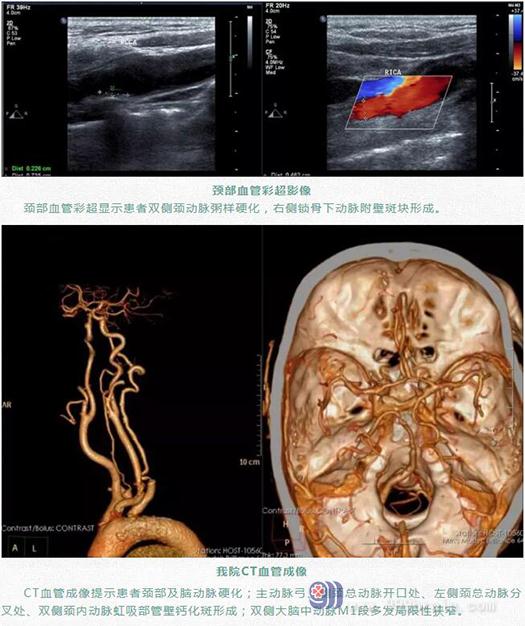

作者:zym 时间:2020-03-02 出处:神经内一科 编辑:lsw 点击次数:4301

当地医院MR检查结果显示,梁大爷是左侧基底节区脑梗死。随后在当地医院治疗了2天,病情仍没有得到明显好转。为寻求进一步治疗,家属带着梁大爷来到广东三九脑科医院神经内一科。

我院神经内一科主任王展航接诊时,发现患者右侧手脚不受控制,一直在“手舞足蹈”。结合外院检查资料和病情,初步诊断为基底节血管病所致偏侧舞蹈症。

入院后,在王展航的指导下,神经内一科叶锦龙医生为患者安排了相关检查。

结合检查结果,并与其他可能导致偏侧舞蹈症的病因相鉴别,最终明确诊断梁大爷是左侧基底节区脑梗塞引起的偏侧舞蹈症。